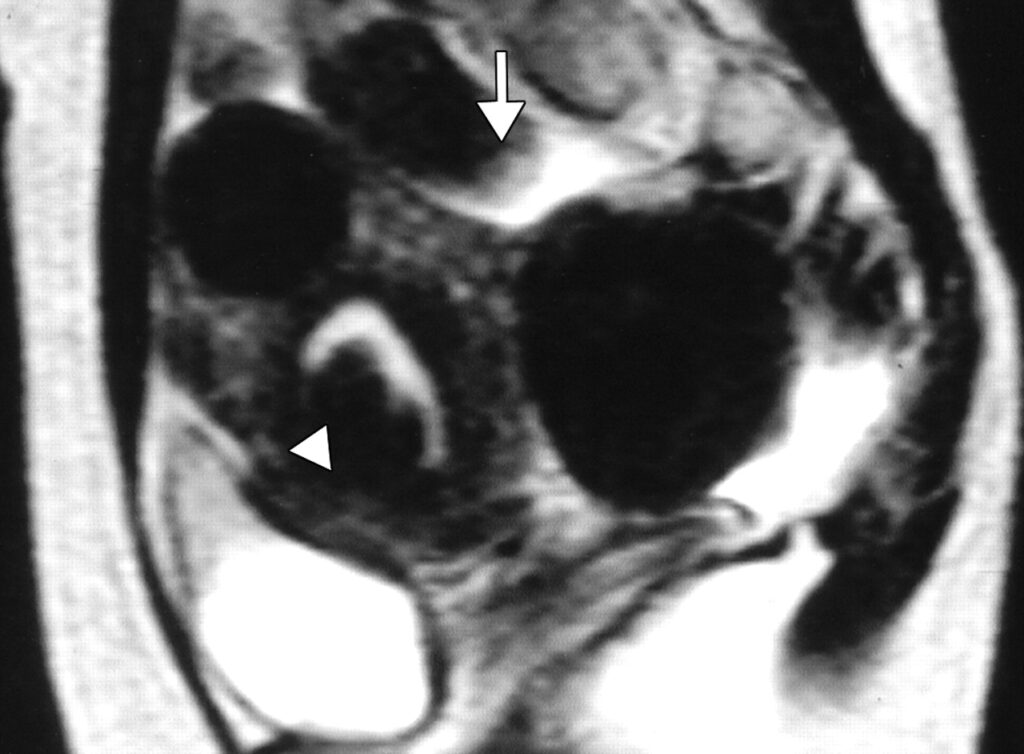

Uterine fibroids are benign tumors that develop in the uterus. While common among all women, fibroids disproportionately affect women of color. Fibroids are the leading cause of hysterectomy, with the average age of women undergoing this major surgery being just 39 years old (Fig. 1).